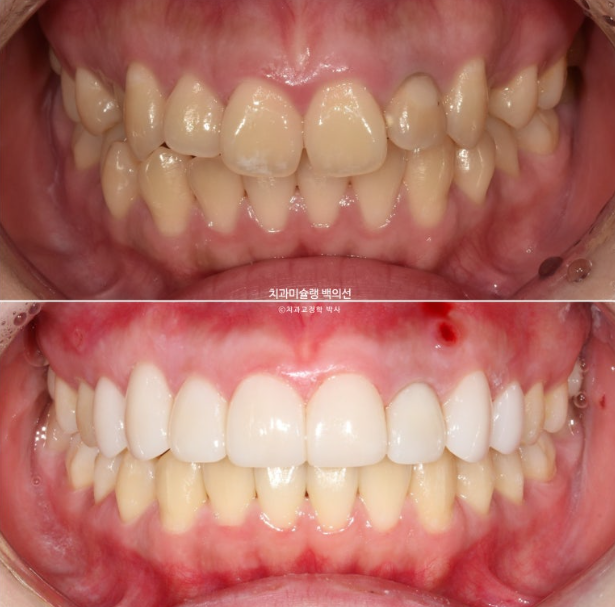

23.12~25.08

맞아진 중심선과 배열의 개선이 보입니다.

반대교합의 개선이 됩니다.

거미스마일과 잇몸돌출의 개선이 눈에 띕니다.